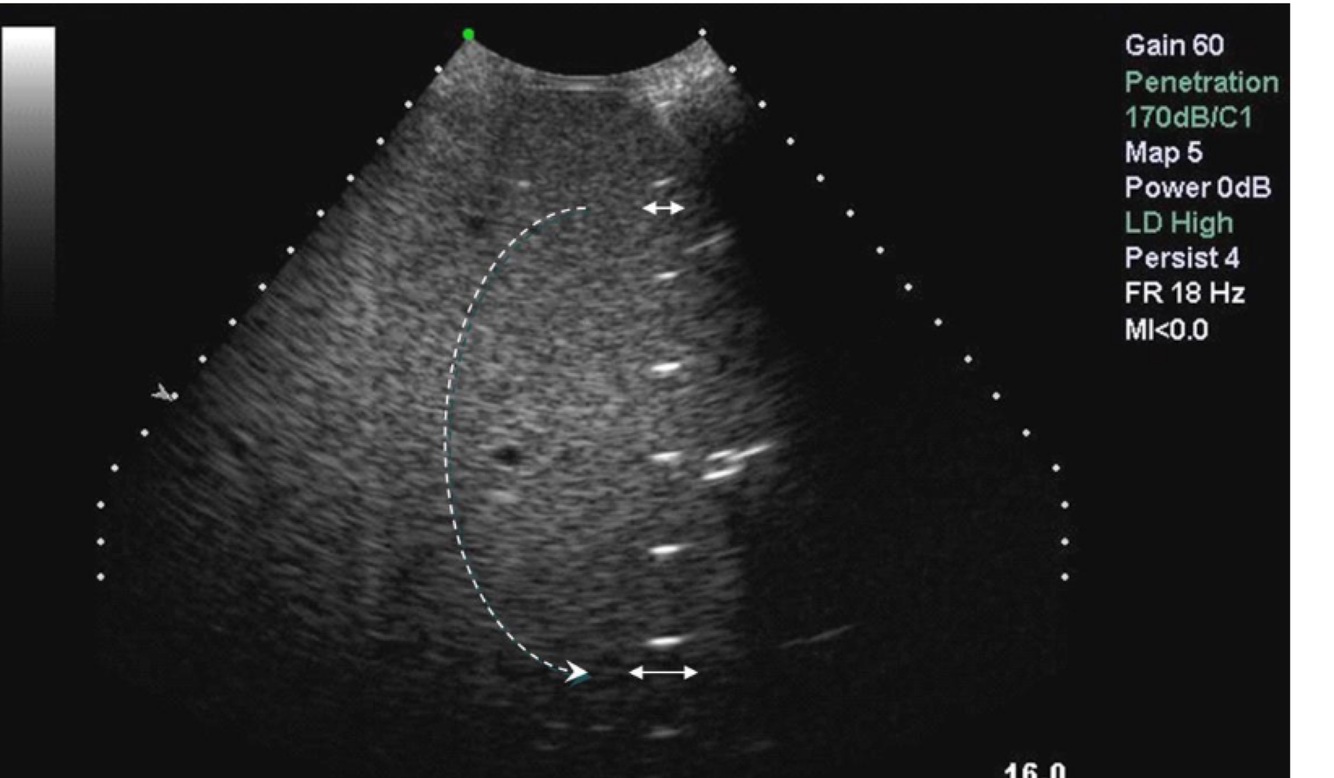

What does this image demonstrate?

A

Slice thickness artifact

21

Q

Slice thickness